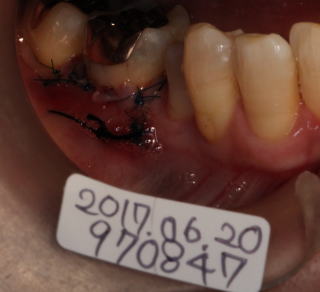

46番の頬側歯肉が歯根分岐部付近まで退縮。

主訴:歯根分岐部部分が時々痛い。また冷たい水がしみる。

歯肉弁歯冠側移動術と頬側に造骨(骨補填剤)を勧める。

術後の写真。